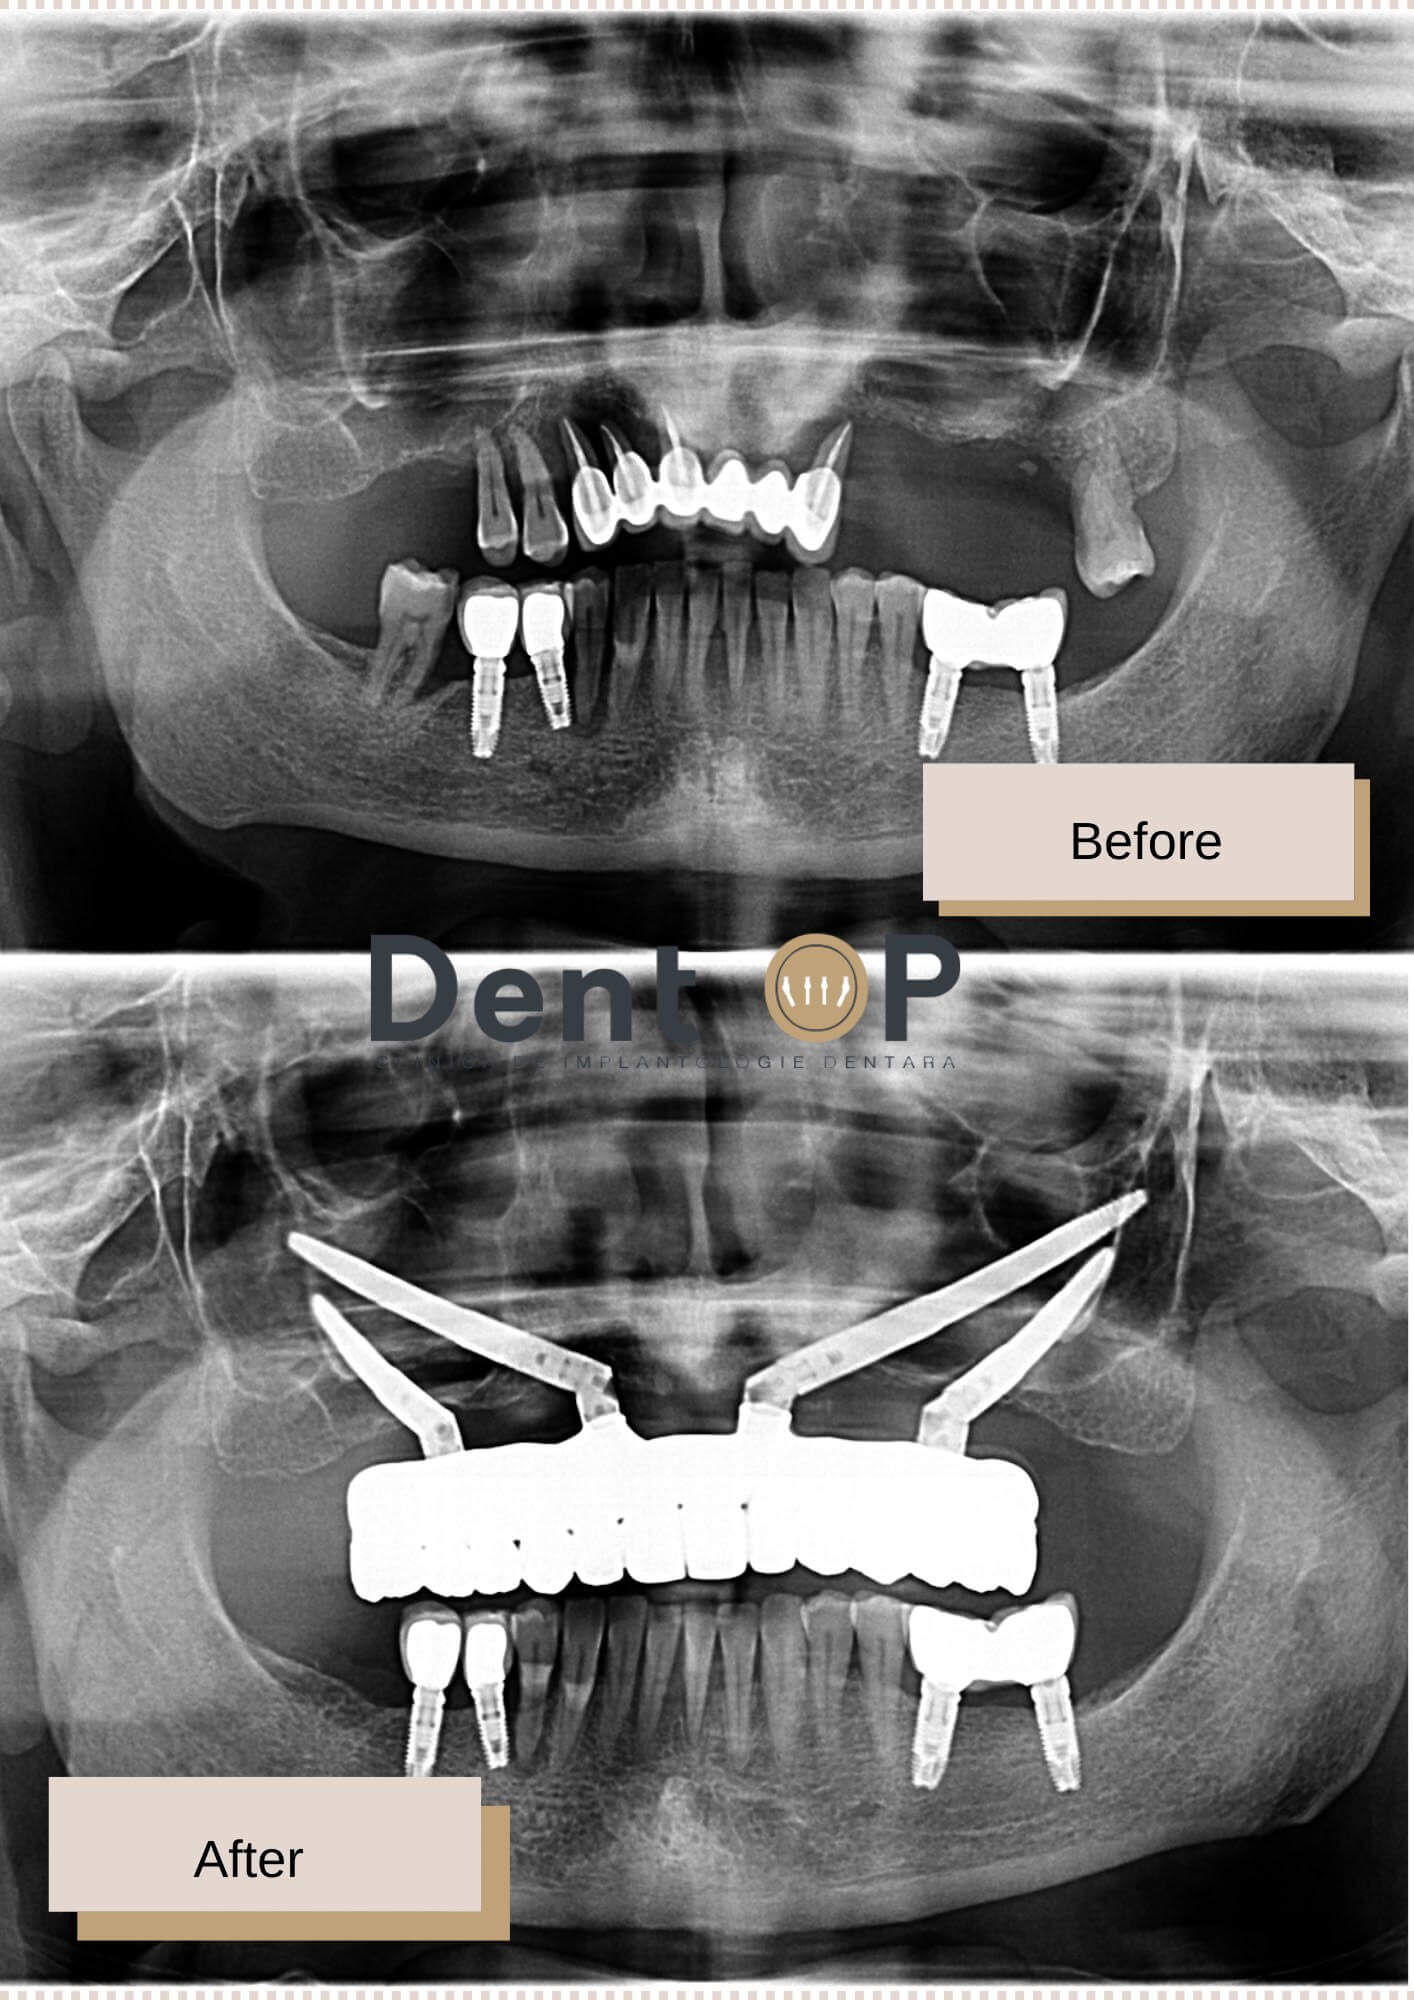

În ziua intervenției, pacienta noastră a beneficiat de 4 implanturi zigomatice la maxilar, deoarece oferta osoasă nu a permis implanturi standard. Deși a fost o intervenție complexă, doamna C. a trecut cu bine peste emoții deoarece a beneficiat și de procedura de Sedare Conștientă, care a ajutat-o să nu simtă durere și nici frică pe parcursul intervenției.

In radiografia de mai jos putem observa cum arată implanturile dentare inserate.